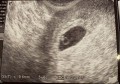

今日、産婦人科行ってきました!! うちのお腹には‥ 6週目に入る赤ちゃんが

心臓が動いてた! めっちゃ感動やった! 来月で結婚一年になりますが! その前に赤ちゃんが産まれる(笑) 今は、子宮の... 続きを読む